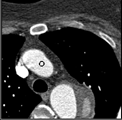

Samples for ascending aorta detection (black circle):

Cluster of candidate points in the ascending aorta.